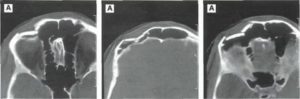

КТ перелома фронтального синуса

Диагностика проводится по клинической картине, результатам КТ.

Диагностика перелома стенки верхнечелюстной пазухи:

- КТ